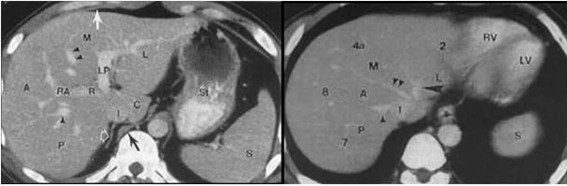

Los VIII segmentos anatómicos hepáticos están definidos por la organización de los sistemas venosos hepático y portal (ver Anexos 2 y 3). Asimismo, cada segmento tiene un flujo circulatorio y drenaje biliar independiente. Por tal motivo es posible eliminar uno o más segmentos y aun así no interrumpir el flujo sanguíneo ni biliar de los demás segmentos.(1)

El hígado se puede dividir en cuatro secciones: la sección anterior derecha (segmentos V y VIII), sección posterior derecha (segmentos VI y VII), sección medial izquierda (segmento IV) y sección lateral izquierda (segmentos II y III) (ver Anexo 4).